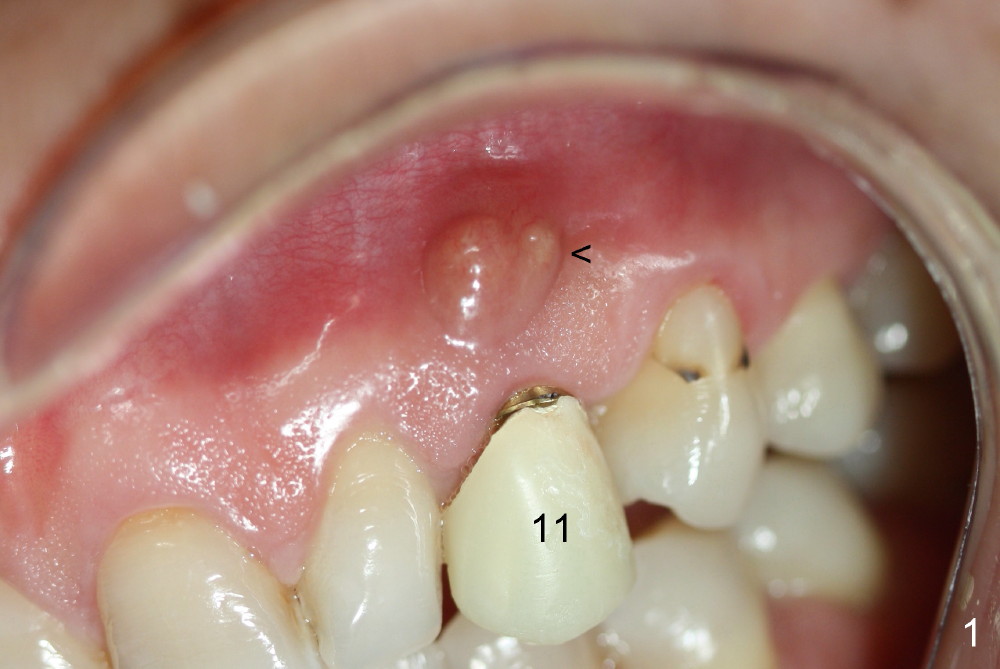

One month post-implantation at the site of the upper left deciduous canine, the patient returns for follow-up with chief complaint "The crown is a little loose. A bubble is becoming smaller". Exam shows an abscess (Fig.1 <) above the provisional (#11). The provisional is loose with mild tenderness. A pull on the provisional leads to dislodgement of the abutment and implant. Raising the buccal flap reveals perforation of the buccal plate with granulation tissue (Fig.2). After debridement (Fig.3), allograft and Osteogen is placed in the defect, followed by Osteotape (Fig.4 *) and suture. This complication can be prevented by CT information. A deciduous tooth socket is small. The immediate implant should be not too large, leaving 2 mm buccal gap. Three months 20 days post graft, the ridge looks not so atrophic (Fig.5). There is no sign of bone resorption (Fig.6). The patient will return for implant placement for the second time soon. Measure the bone width with bone caliper after local anesthesia. Fully expose the alveolus. Start osteotomy as palatal as possible. Repeatedly check osteotomy position and trajectory. Use surgical stent. The implant will not be too long or too wide. Is the ridge as wide as clinically shown?